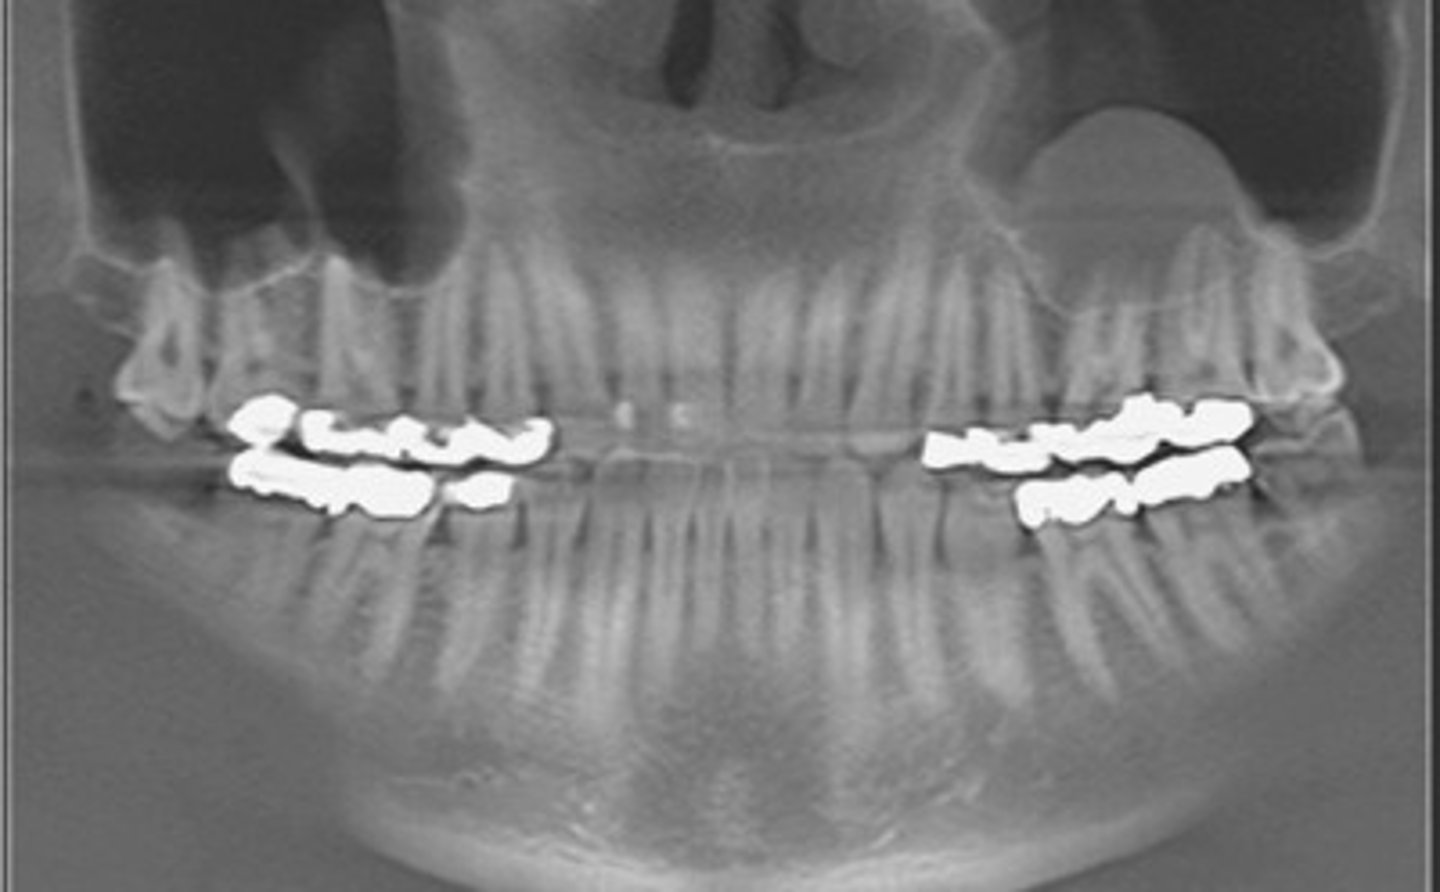

Panoramic xray with radiopacity underneath the mandibular incisors, asked what

was it?

supernumerary tooth

(other choices- odontoma, impacted insicor)